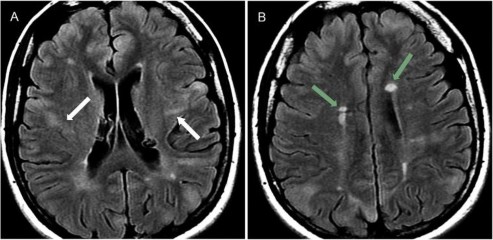

Hình 1.7. Xơ hóa hồi hải mã trái kèm teo thùy thái dương bên trái

Nguồn trích dẫn: Hiba AH, Lawrence JH. Uptodate. 2018; Topic 14040 [29].